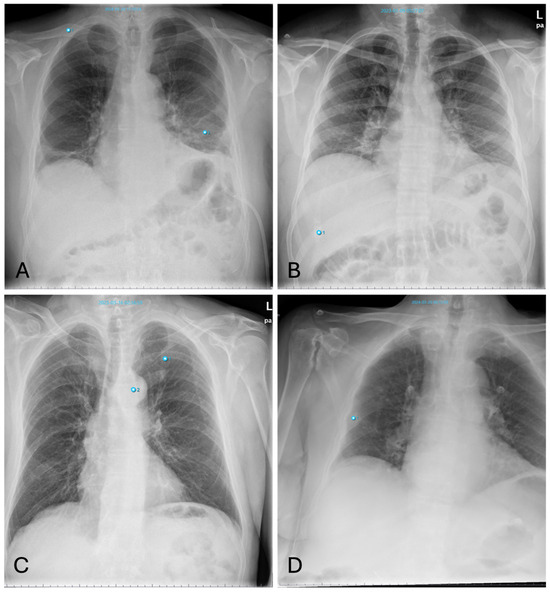

Mirroring the standard human diagnostic process, all written reports meeting the eligibility criteria were processed with the AI software. An example output is shown in Figure 1. These diagnoses were extracted by a medical student as binary variables and represent the first rating to be analyzed in this study.

Figure 1. Chest radiograph analyzed with AI. AI-generated report based on a routine chest radiograph marking two findings together with their precise locations: one lung abnormality (1) and one aortic abnormality (2). All findings are listed on the right side, along with an overall abnormality probability score of 60%. Below the list is a concise report created by the software, similar to a radiology report.